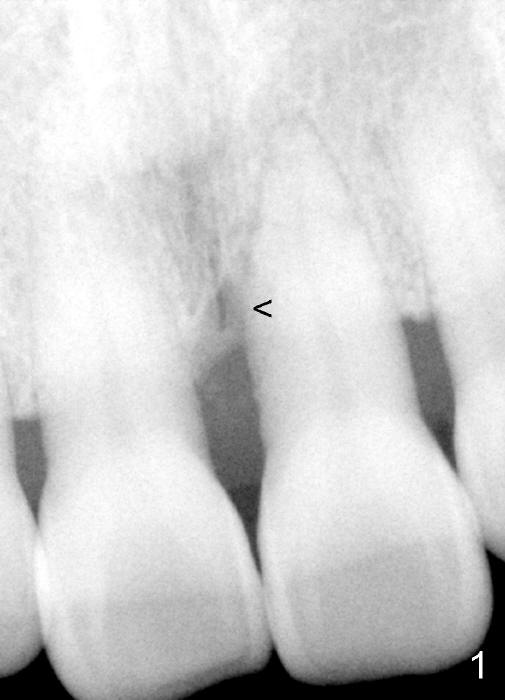

A 60-year-old lady had an abscess mesial to #9 six years ago (Fig.1,2 <), treated as a perio lesion by laser (Fig.3) and osseous surgery without bone graft (Fig.6, followed by CT exam revealing semi-circumferential bone loss (Fig.4,5). When the perio treatment failed, attention was paid to endo aspect (Fig.7-9). In fact the pulp was found to be vital when access to root canal therapy was made. As expected, the treatment failed again. The palatal fistula persisted. The infection was suspected to be a source of remote immediate implant site (#30). The tooth #9 was extracted. It appears that there is a semilunar crack line in the linguomesial root (Fig.12). When the socket healed 2 weeks post extraction (Fig.10), the #30 buccal defect was debrided with bone graft. There was no bone resorption 4 weeks post extraction (Fig.11); a 4.5x17 mm implant was placed (Fig.13-15). An immediate provisional was fabricated (Fig.16-18). Fig.19,20 were taken 3 months post implantation and 7 months post cementation, respectively. Dense bone forms around the implant coronally 4 years 5 months post cementation (Fig.21), while the gingiva is healthy palatally (Fig.22) and buccally (Fig.23).